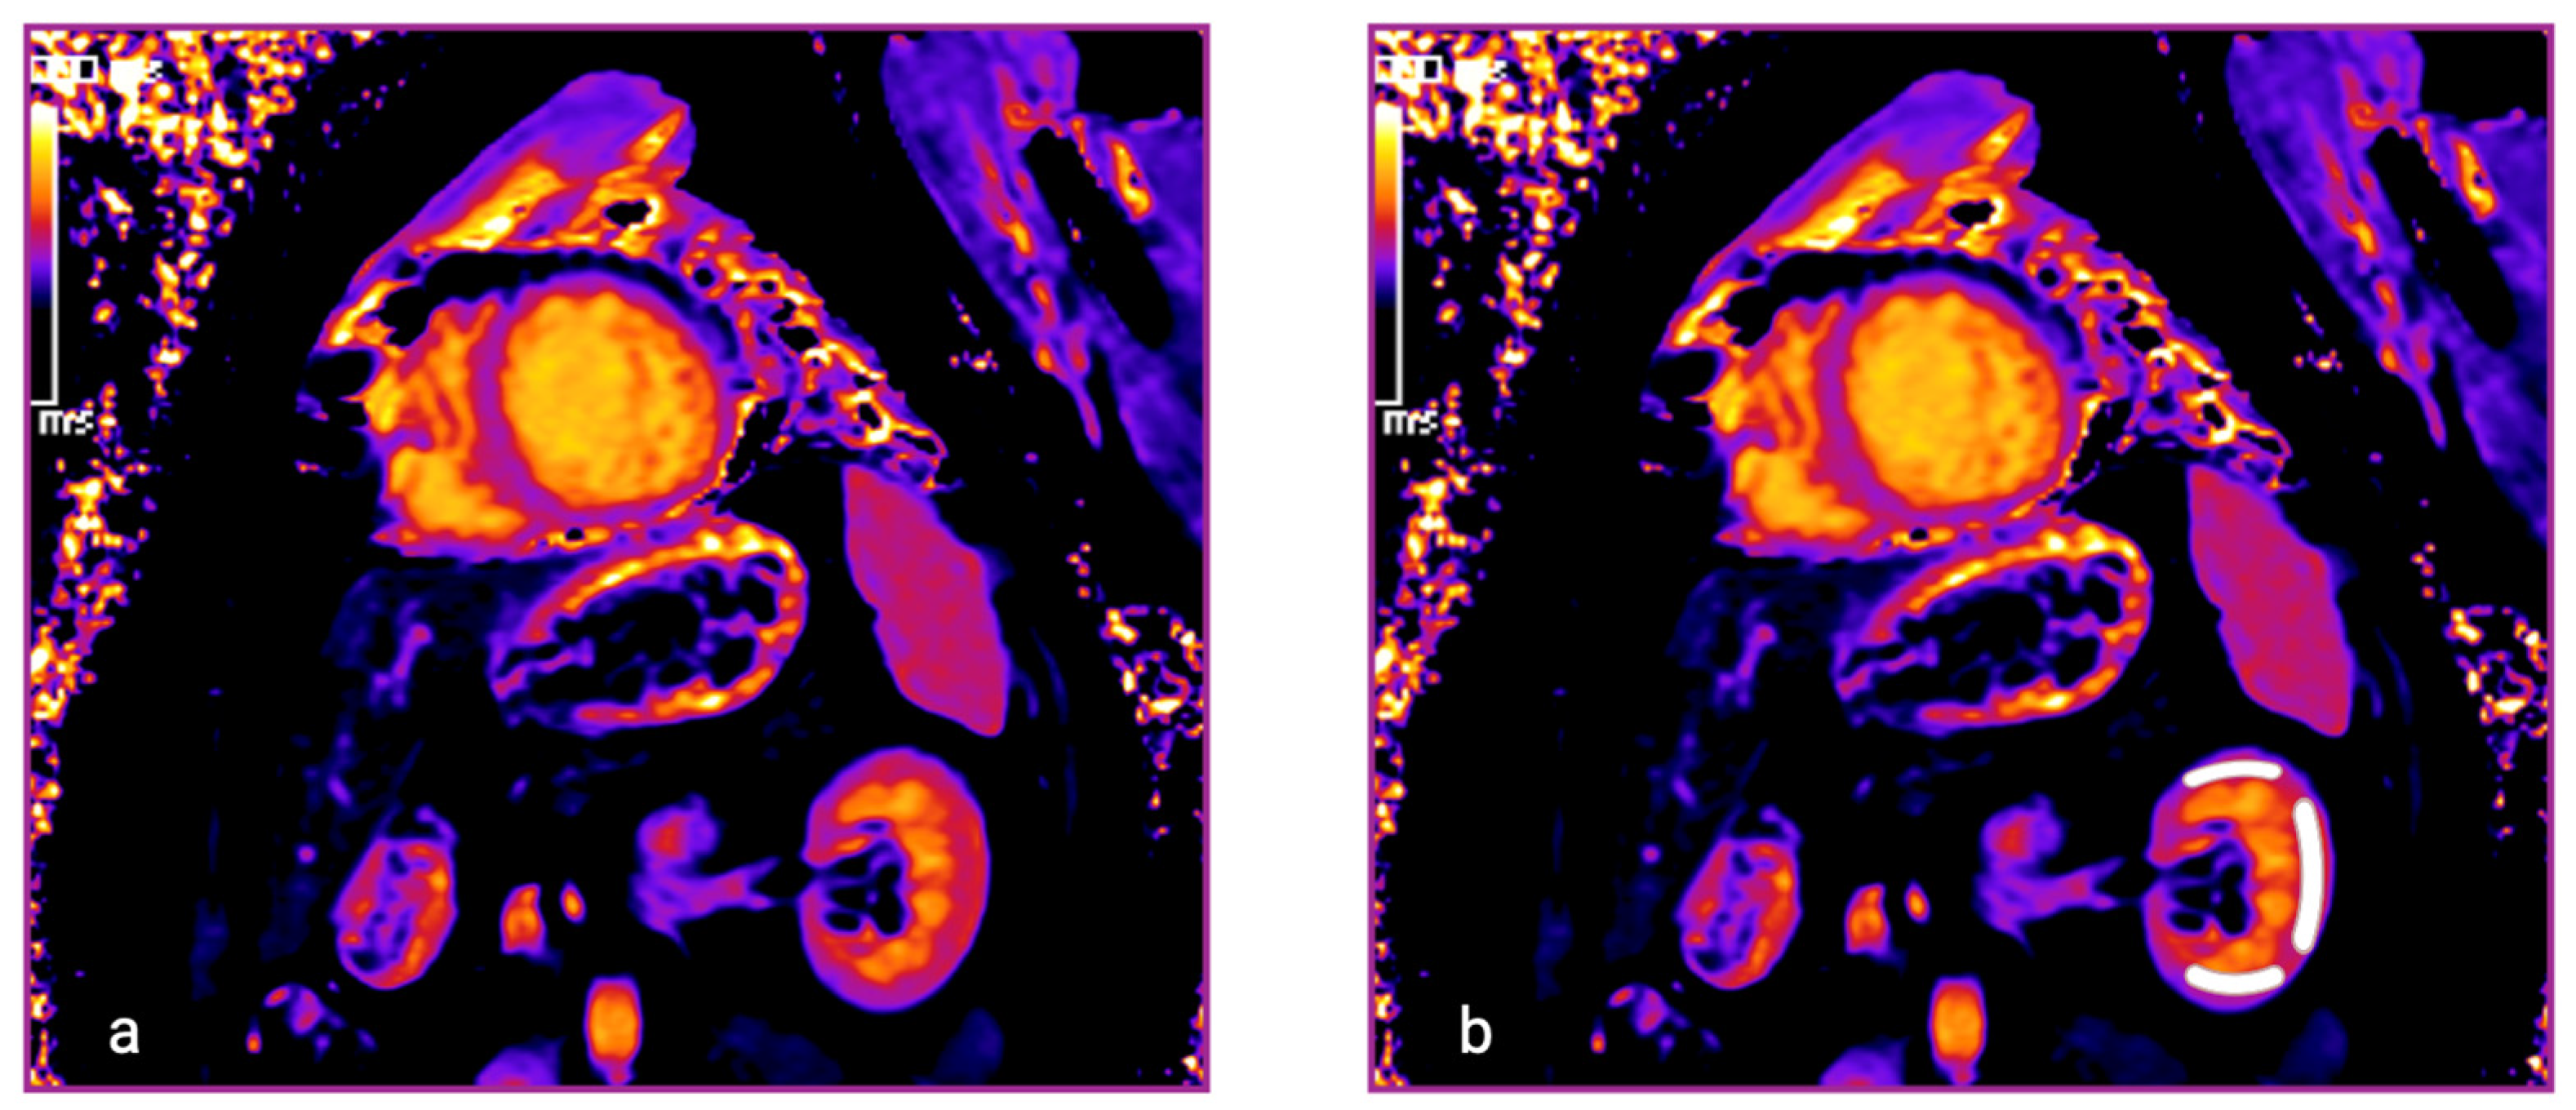

2.3. Definition of Renal T1 Times